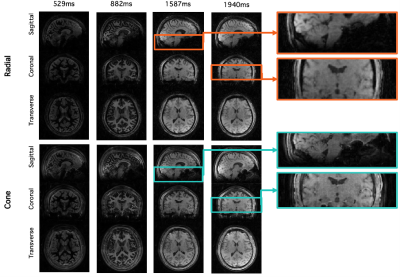

Fig. 3 compares angiographic images acquired in the same subject using cone and radial trajectories. The cone trajectory allowed depiction of the proximal arteries much better than the radial trajectory, probably due to reduced flow or B0-based dephasing at the much shorter echo time of the cone trajectory. The small vessels are also better visualized by the cone trajectory thanks to better sampling in the k-space periphery.For perfusion images reconstructed from the same raw k-space data (Fig. 4), the cone trajectory also provides better spatial resolution than the radial trajectory with an additional increase in SNR. The small structures are now clearly visible in the cone case.Using the mean rather than difference between label and control data, structural images were also reconstructed (Fig. 5). Images with varying T1-weighted contrast are produced at different times after the inversion pulse, but as above, the cone trajectory provides better resolution and SNR.In conclusion, a 3D cone trajectory can be integrated into the 4D CASPRIA framework, improving spatial resolution and SNR and allowing high quality time-resolved angiograms, perfusion images and T1-weighted structural images to be obtained from a single 6-minute scan. A quantitative comparison in a larger number of healthy controls to confirm these results will be performed in future work.

Fig. 5. Comparison of structural images between radial and cone trajectories at three example timepoints. Note the variation in T1 contrast due to recovery of the static tissue after the background suppression pulses during the course of the readout. The zoomed sections show that detailed structures are more easily visible in the cone case.